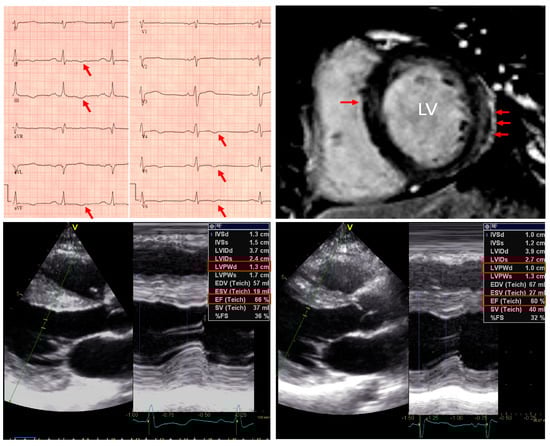

- Yilmaz, A.; Gdynia, H.J.; Baccouche, H.; Mahrholdt, H.; Meinhardt, G.; Basso, C.; Thiene, G.; Sperfeld, A.D.; Ludolph, A.C.; Sechtem, U. Cardiac involvement in patients with Becker muscular dystrophy: New diagnostic and pathophysiological insights by a CMR approach. J. Cardiovasc. Magn. Reson. 2008, 10, 50. [Google Scholar] [CrossRef]